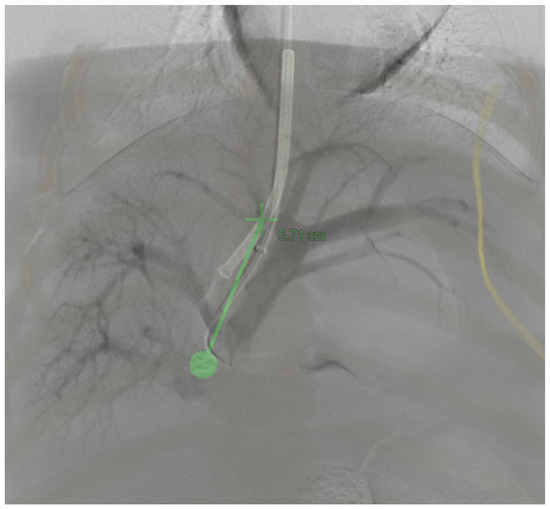

3.3. 3D Angiography-Guided TIPS Using CBCT/Angiography-Fused Images